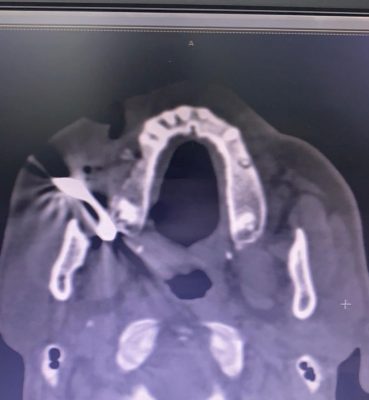

تمكن فريق طبي بقسم جراحة الوجه والفكين بمستشفى أبها الخاص العالمي بعسير ، من إجراء عملية جراحية لإنقاذ مقيم بالعقد الرابع من العمر بعد إصابته في الوجه أثناء عمله بمهنة الحدادة مما أدى إلى شقوق عميقة بأنسجة الخد والشفة ونزيف حاد بالأوعية نتيجة دخول اجسام معدنية .

في هذا الإطار أوضح الدكتور فؤاد العُمري استشاري جراحة الوجه والفكين أنه تم إجراء عملية ايقاف نزيف الاوعية الدموية، وإزالة الاجسام المعدنية والمسامير بالوجه ،وإغلاق الجروح تجميلياً دون أي مضاعفات ولله الحمد ، مضيفاً : اُجريت الجراحة من خلال الفريق الطبي برئاستي ، بالإضافة إلى الدكتورة هند عبدالناصر اخصائية التخدير بالمستشفى، ولقد تمت متابعة استشفاء المريض وينعم بصحة وعافية.

مشيراً إلى أنه تم التأكد من استعادة الوجه لوظائفه الحيوية والشكل الطبيعي ، حيث تم ذلك من خلال استخدام الأساليب التكنولوجية لتقديم أفضل نتائج التجميل، مبيناً أن جراحة تجميل الوجه تساعد على تصحيح العيوب وضبط نسب منطقة معينة ، مع إصلاح النتوءات أو التورمات أو غير ذلك من الأمور التي تعكّر الثقة بالنفس مستقبلاً. كما تتيح الإجراءات الجراحية تحقيق تغيرات بنيوية، وترميم ملامح معينة في الوجه، وتعزيز المظهر الطبيعي.